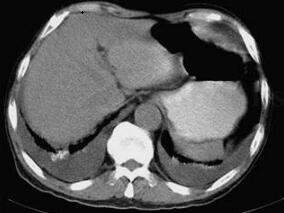

1小时条评论以下病例中,患者患缺血性肝炎(ischemic hepatitis),又称缺氧性肝炎(hypoxic hepatitis),在普通病房极罕见。大多数病例为重症监护室的病危患者,您知道常继发于哪些疾病吗? 男性,76岁。 【主诉】 胸闷、憋气间作5年,加重伴咳嗽、咯痰10天。 【现病史】 ...